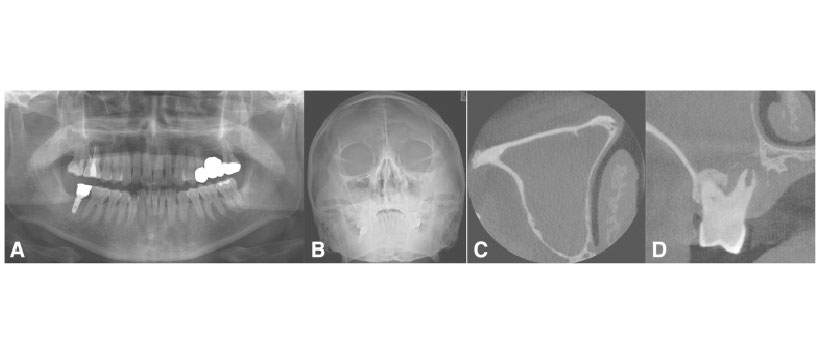

Figura 4: Un caso de sinusitis maxilar odontogénica que se origina en un diente que tiene un quiste enorme en el seno maxilar derecho. Vista panorámica preoperatoria (a), vista de Water (b), vista de TC coronal que muestra una masa quística expansible ósea con obstrucción del ostium (c) y vista de TC axial que muestra la masa expansiva posterior (d)